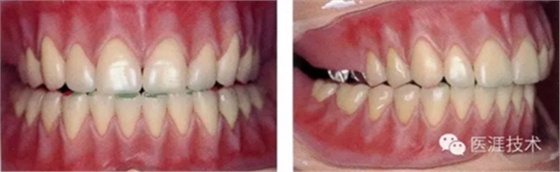

12,2周后拆線,患者口腔內(nèi)的實(shí)際狀態(tài)

15,歷經(jīng)5個(gè)月的調(diào)整(定期來(lái)院更換組織面調(diào)解劑,每次不超過(guò)1個(gè)月),口腔內(nèi)實(shí)現(xiàn)穩(wěn)定狀態(tài),牙槽骨不在吸收。使用臨時(shí)義齒直接取最終印模制作技工模型。